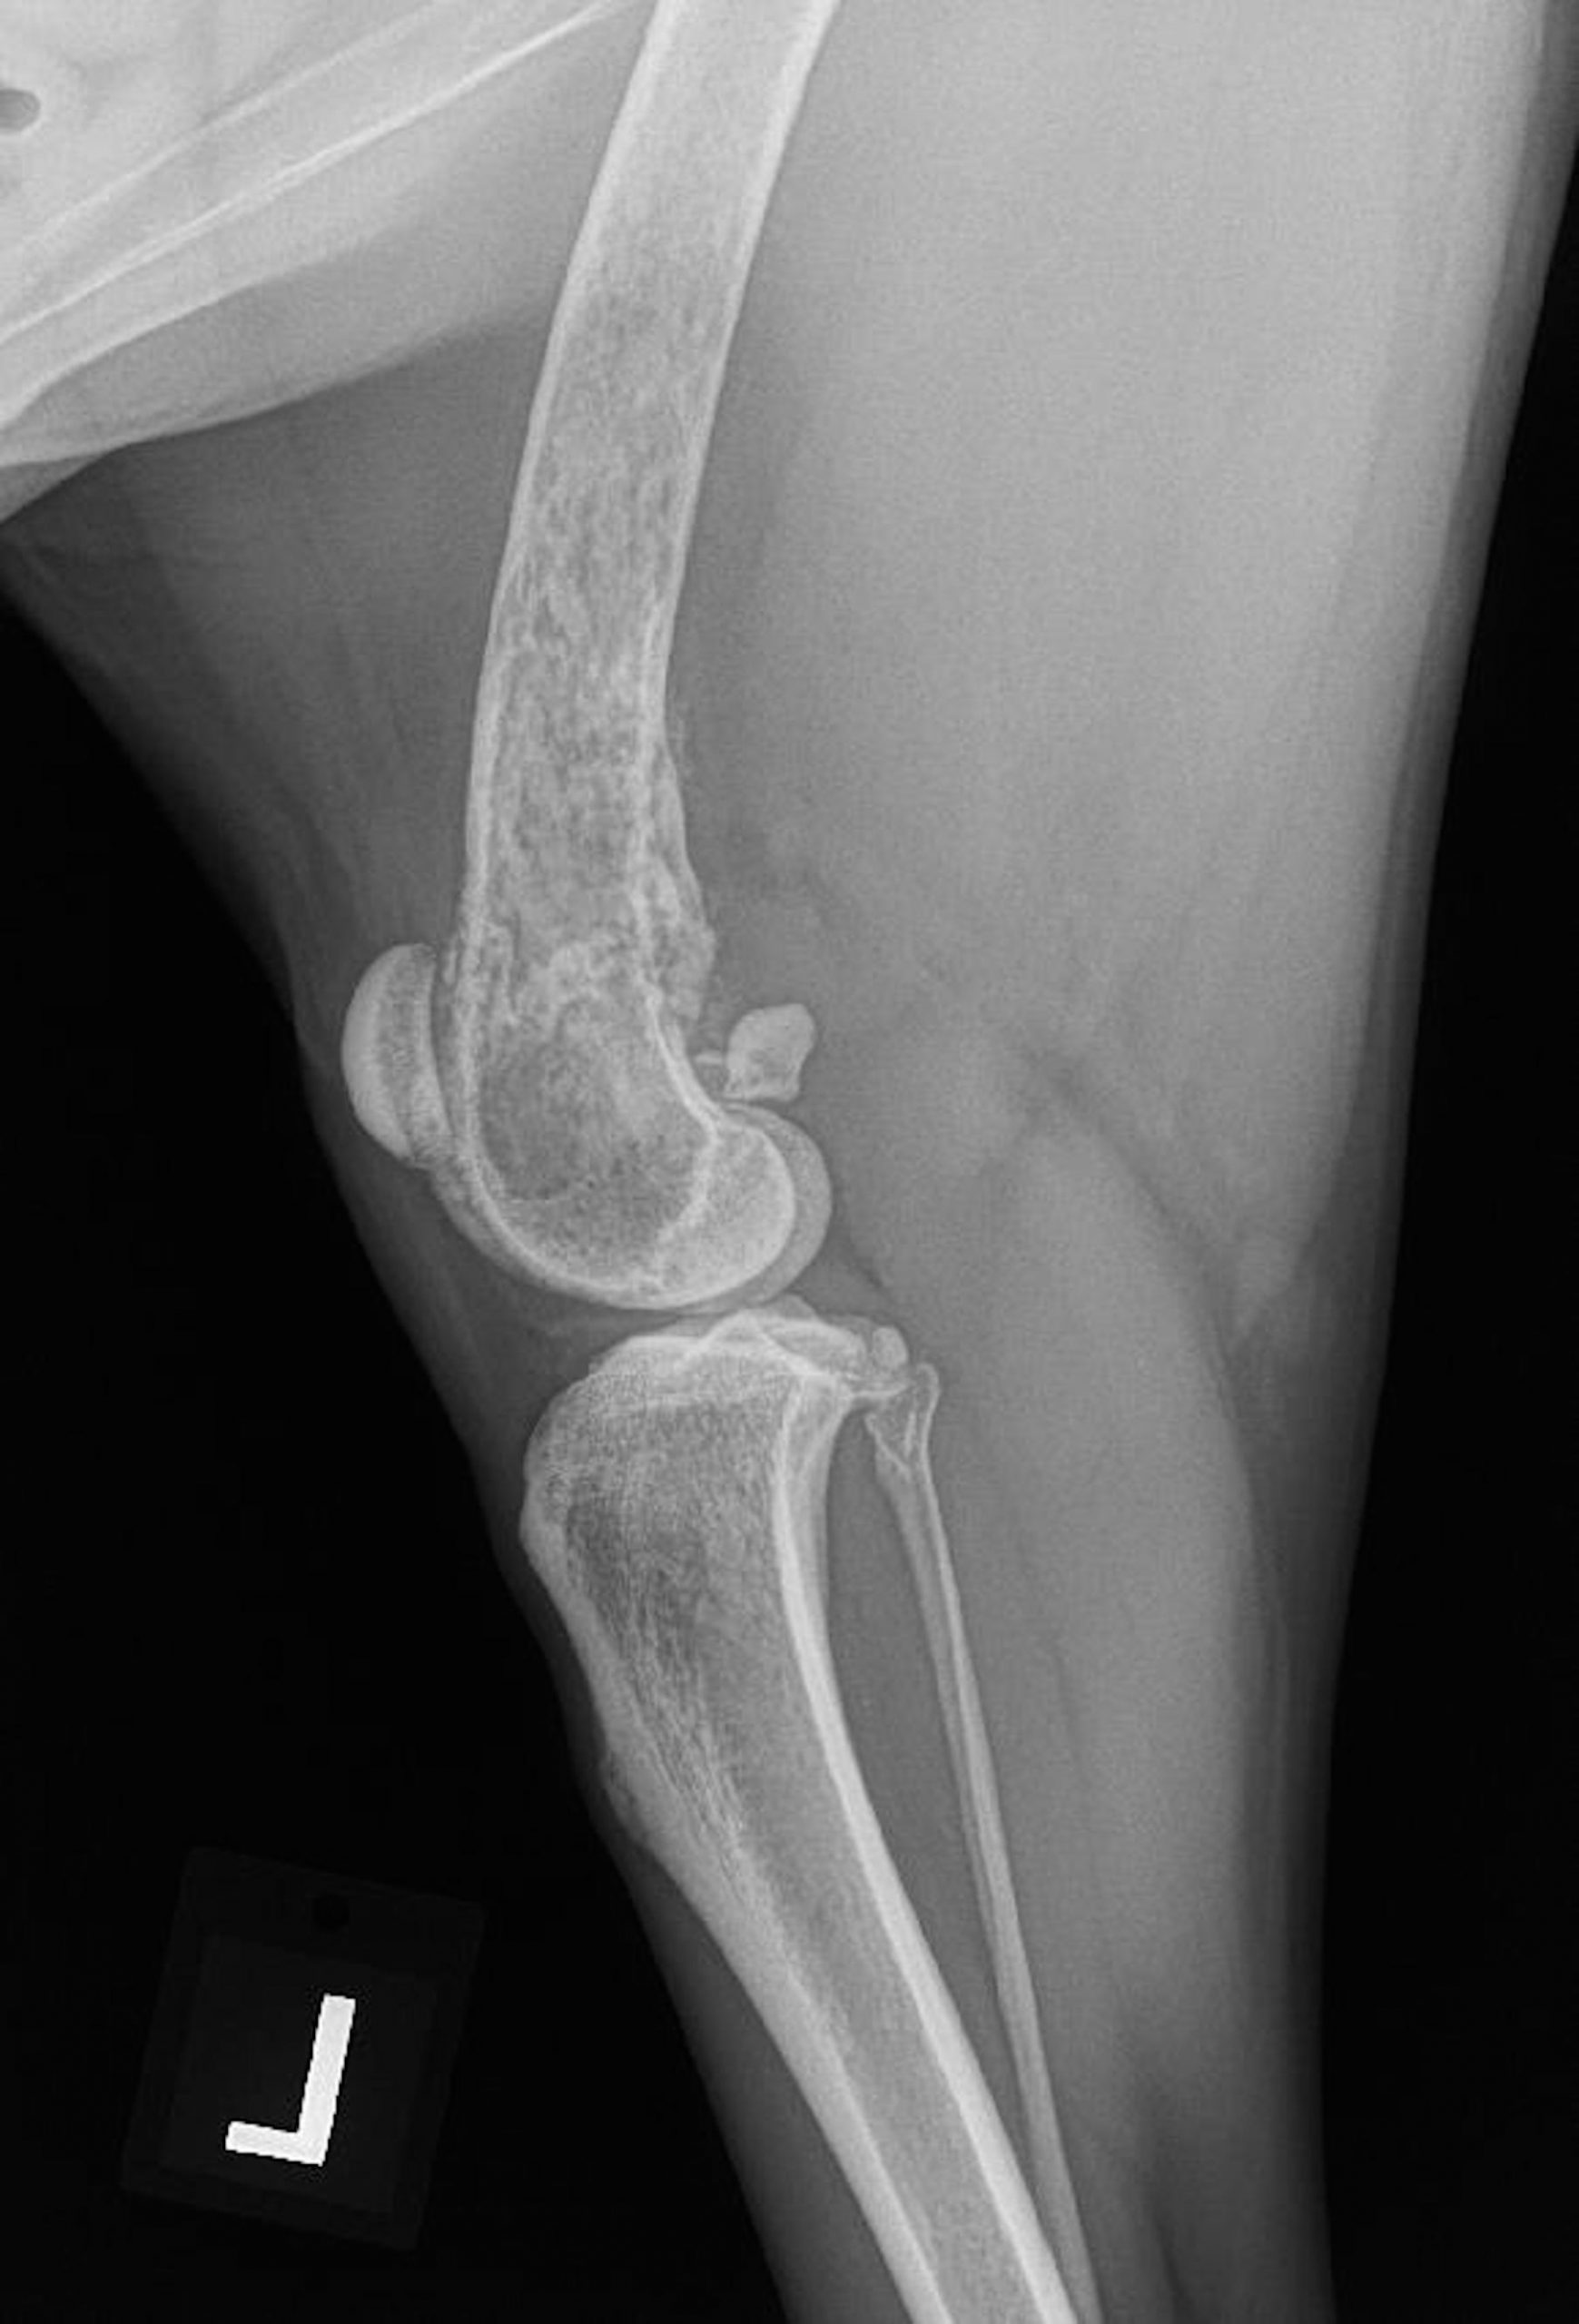

If you or someone you know has been diagnosed with ovarian cancer, learn all the essential information needed to understand this condition and what to expect from treatment. Canine Appendicular Osteosarcoma • MSPCA-Angell

Canine Appendicular Osteosarcoma • MSPCA-Angell from www.mspca.org